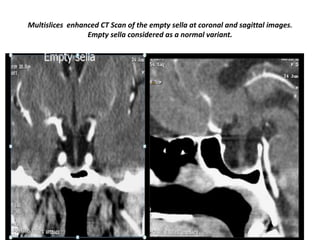

Multislices enhanced CT Scan of the empty sella at coronal and sagittal images.

Empty sella considered as a normal variant.